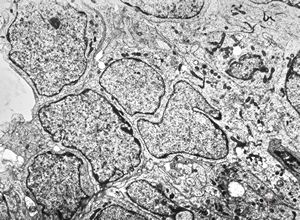

F,50y. | progressive multifocal leukoencephalopathy- viral particles in a glial cell

F,50y. | progressive multifocal leukoencephalopathy- viral particles in a glial cell

F,50y. | progressive multifocal leukoencephalopathy- viral particles in a glial cell